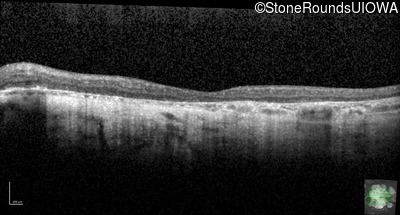

Age at visit: 43 years

OD OS